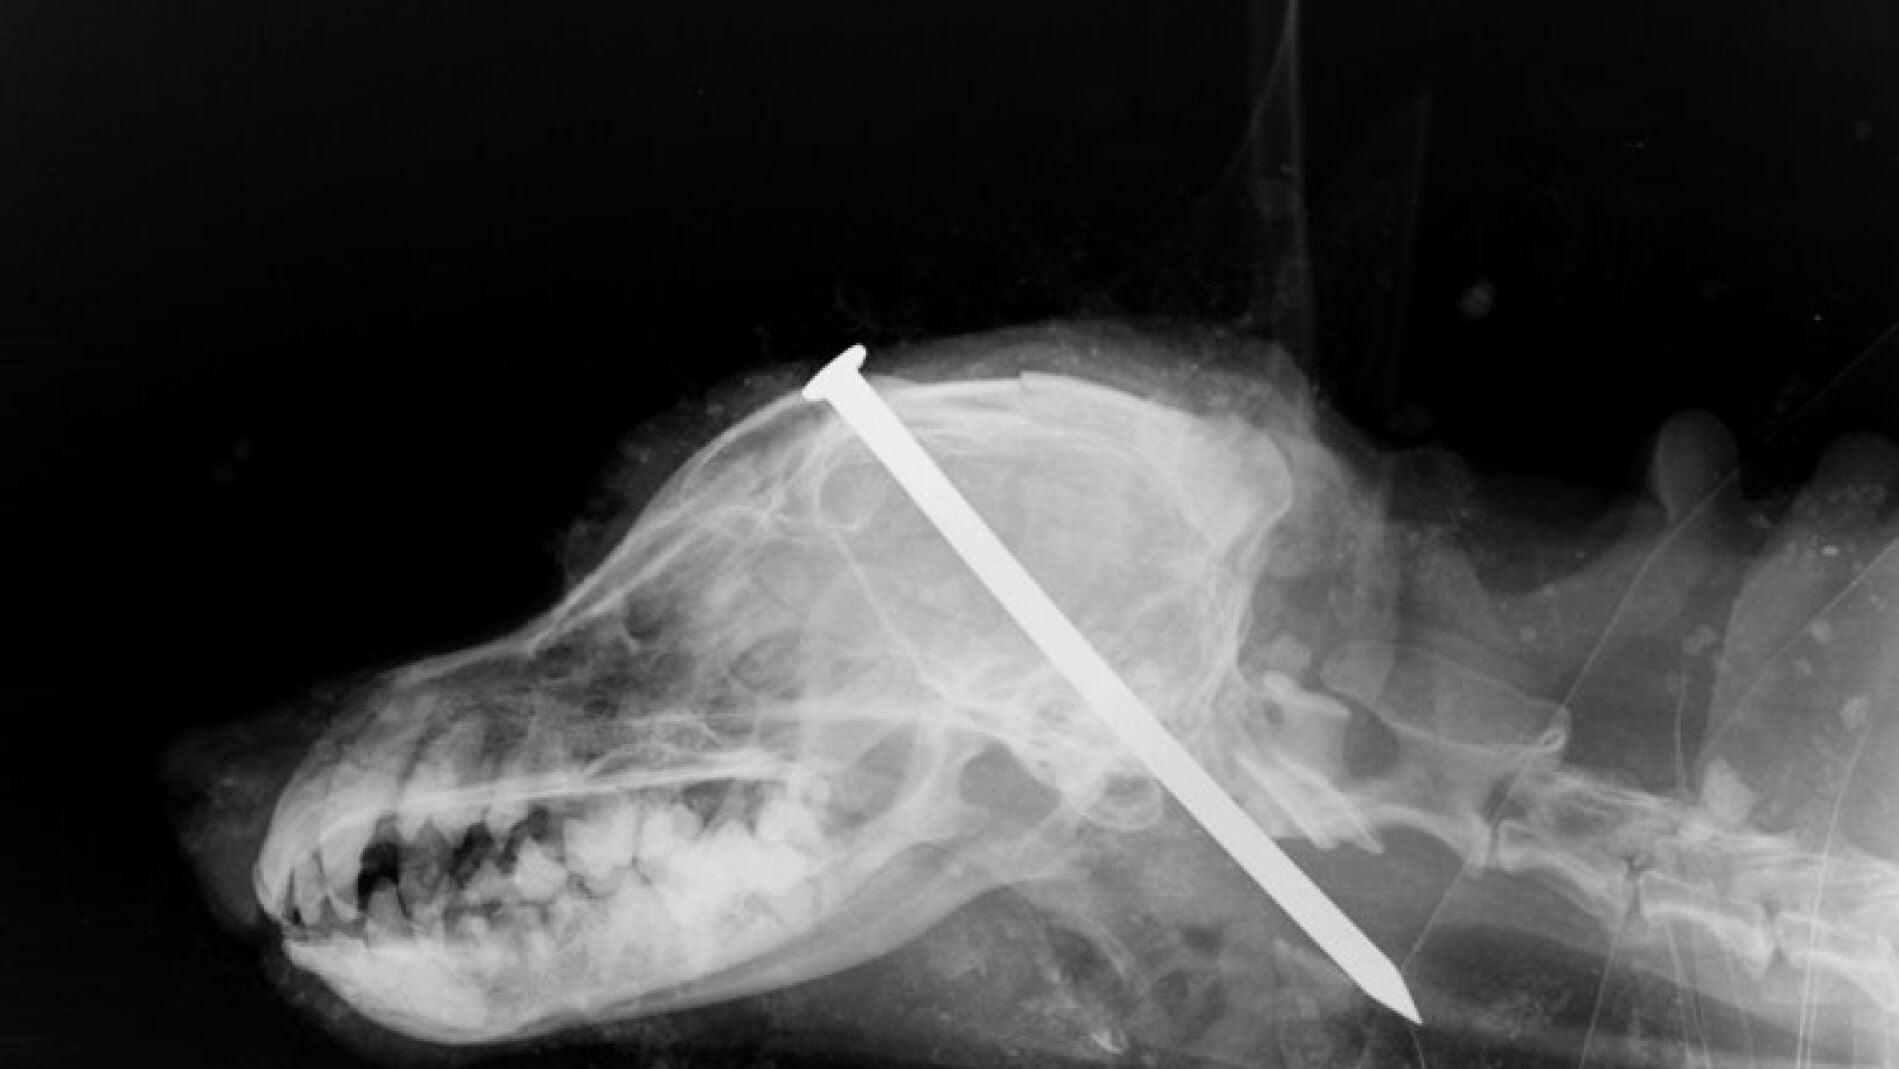

El perro estaba enterrado bajo un montón de tierra y tenía un clavo en mitad de la cabeza, entre los ojos. Tras ser encontrado por una pareja que paseaba cerca de donde estaba enterrado, fue llevado al veterinario, donde finalmente murió.

Una pareja que caminaba por el campo en el norte de Yorkshire ha encontrado un perro enterrado vivo con un clavo entre los ojos. El animal, que parece ser una mezcla de terrier, estaba bajo un montón de tierra llorando. Con una pala, la pareja excavó para sacar al perro, que estaba vivo pero exhausto.

La Real Sociedad par ala Prevención de la Crueldad Animal ha publicado fotografías del suceso, para ayudar a encontrar a los responsables.

El inspector de la RSPCA Nick Jones, explicó que después de diez años al servicio de la institución, nunca había visto algo tan horrible e inexplicablemente cruel. "Es un acto de crueldad y es inconcebible encontrar una explicación de por que alguien ha hecho esto".